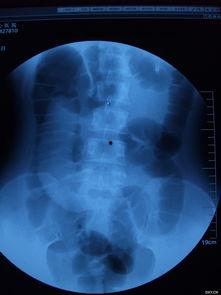

1. 影像学检查:如X光、CT、MRI等,可以清晰地显示肠套叠的情况。